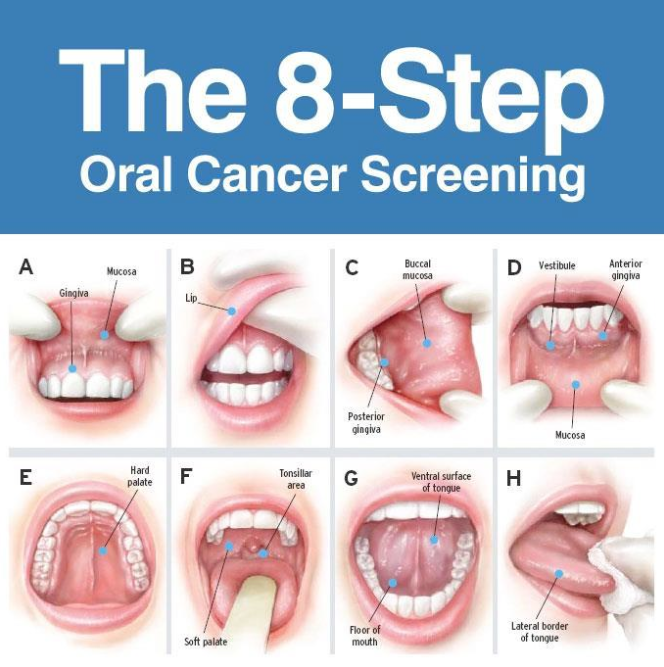

10 Steps To Perform An Oral Cancer Screening Dentistryiq

Making Oral Cancer Screening A Routine Part Of Your Patient

Self Oral Cancer Screening Socs Education Program School

Self Oral Cancer Screening Socs Education Program School

Self Oral Cancer Screening Socs Education Program School

Self Oral Cancer Screening Socs Education Program School

Self Oral Cancer Screening Socs Education Program School

Self Oral Cancer Screening Socs Education Program School

Six Step Screening Eva Grayzel

Faces Of Oral Cancer Six Step Screening